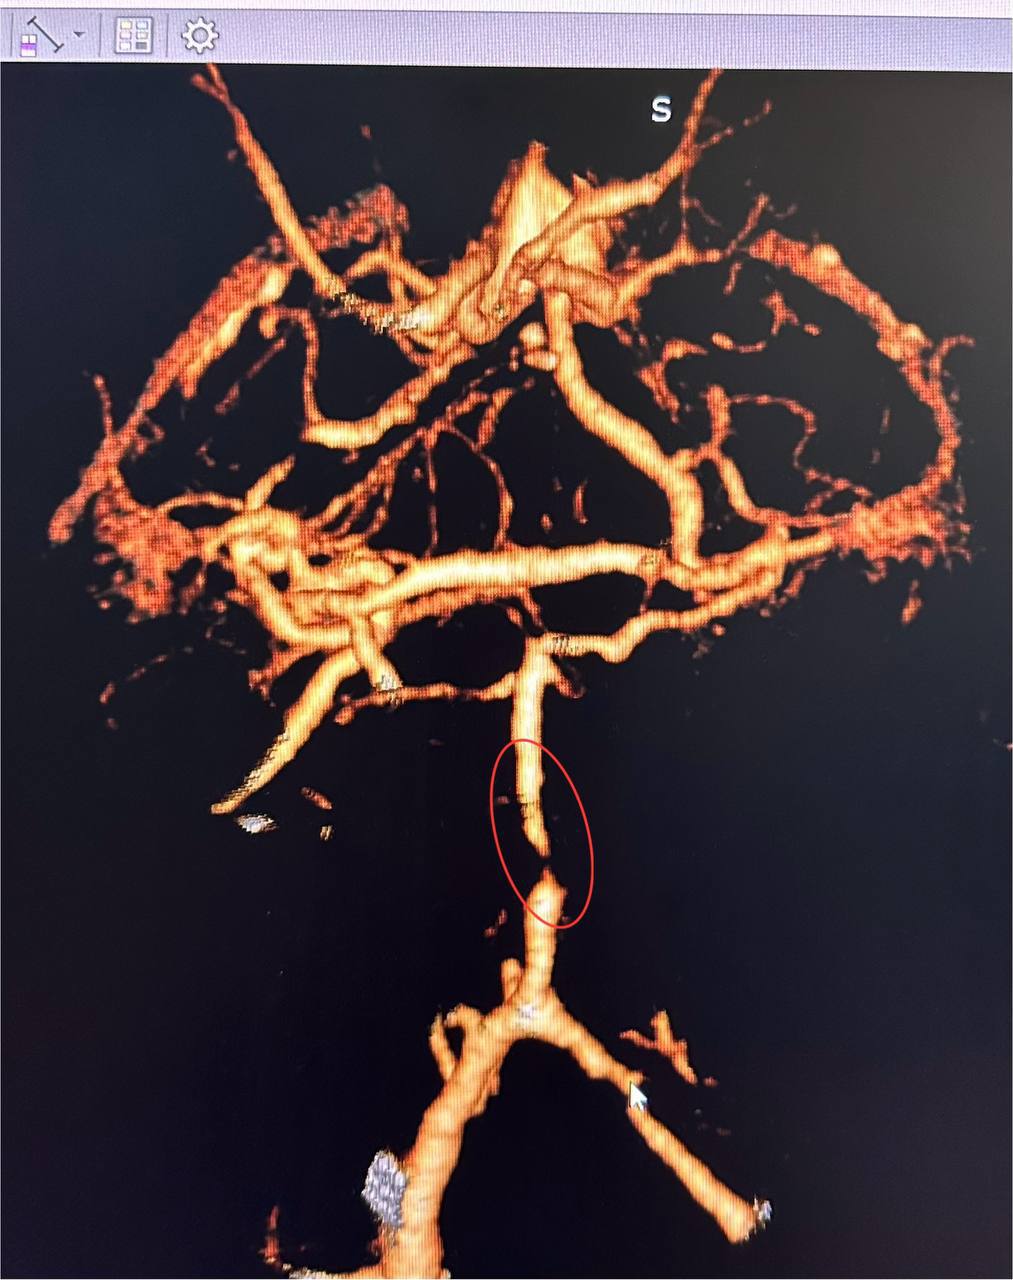

Як розповів завідувач рентгенендоваскулярним блоком лікарні Олександр Скрипка, це був один з найскладніших випадків – ураження стовбурової частини мозку. Базилярна артерія була майже повністю закрита атеросклеротичною бляшкою. Такі інсульти належать до найбільш небезпечних.

Фахівці прийняли рішення провести ангіопластику артерії. Десята лікарня має досвід такої методики лікування в кардіології при атеросклерозі коронарних судин, але застосування її для мозкових судин – це іноваційна технологія для України.